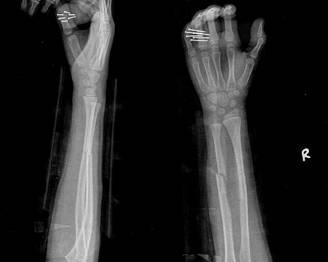

摘要:最新尺橈骨融合方法展現(xiàn)骨頭間的奇妙和諧與友情力量。通過先進的醫(yī)療技術(shù),尺骨和橈骨之間的融合得到顯著改善。這種方法不僅提高了治療效果,還展現(xiàn)了人體骨骼之間的和諧關(guān)系。憑借友情和信念的力量,醫(yī)學(xué)界不斷突破,為患者帶來福音。

在醫(yī)生的介紹下,他們了解到了一種最新的尺橈骨融合治療方法——通過微創(chuàng)手術(shù)進行骨骼融合的新技術(shù),這種方法不僅減少了手術(shù)風(fēng)險,還能更快地恢復(fù)活動能力,雖然小明感到害怕,但他的朋友們一直陪伴在他身邊,給予他勇氣和力量。